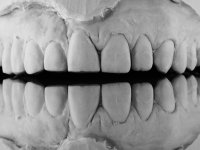

Fixed partial denture between teeth 15 and 11, using teeth 14, 13 and 11 as abutments. Teeth 12 and 15 were planned as ovoid pontics. The framework material chosen was zirconia and the veneering ceramics should have a gum-shade component to rehabilitate the soft-tissues.

After the root canal treatment of tooth 11, dental impressions were taken to do a fixed provisional (reinforced) acrylic prosthesis. The provisional bridge included an acrylic component with a gum-shade color, to evaluate the integration of the treatment plan, in relation to function and esthetics. The preparation of teeth 14 and 13 were minimal invasive, with supra-gingival finishing lines, preserving enamel at its uttermost. Tooth 11 was prepared in a conventional way, with an intra-sulcular margin. The provisional bridge was rebased intra-oral with an autopolymerized acrylic. After 4 weeks, a dental impression with a double mixture technique was done. In the dental lab, CAD-CAM technology was used to produce a zirconia framework. In the provisional bridge, it was noted by the patient, and by ourselves, the need for symmetry in the dimensions and shape of the teeth, in relation to their homologues of the 2nd quadrant. Accordingly, a mirror effect was selected in the CAD design of the framework, to mimic in the prosthetic structure the dimensions and shape of the homologous natural teeth. Framework design included also a small zirconia wing covering the palatal surface of the non-prep tooth 21. This wing serves as an additional support and, simultaneously, avoids an eventual occurrence of a future diastema between central incisors. Color selection of teeth and soft-tissues was done by the ceramist in the dental office. After evaluation and approval of the prosthetic work placed in mouth, the dental bridge was bonded. This bonding procedure was optimized by the addition of a zirconia liner in the inner surface of the framework and in the internal surface of the wing. This treatment proved to be esthetically acceptable and functionally able, with a strong contribution to the patient’s self-esteem.